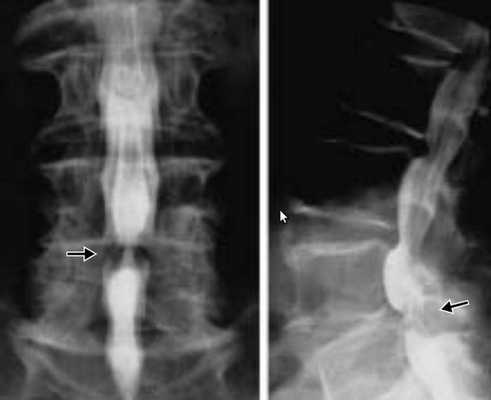

Рентгенография рентгеновские лучи позволяют, получит двухмерное изображение позвоночника. Рентгенография может быть назначена как первый метод исследования, особенно помогая диагностировать травмы или опухоли. Рентгенография позволяет визуализировать структуру позвонков конфигурацию суставных поверхностей обнаружить кальцинаты.

Миелография представляет собой разновидность рентгенографии, но только при миелографии в спинномозговой канал вводится контрастное вещество. Это позволяет визуализировать наличие стеноза опухолей, остеофиты или признаки давления на спинной мозг грыж дисков.

Функциональная спондилография поясничного отдела от 12.02.2019: остеохондроз II степени; спондилоартроз; нестабильность сегментов на уровне L4-L5 и L5-S1; ретролистез — смещение L5 позвонка назад — I степени. Электронейромиография (ЭНМГ) от 12.02.2019: малоберцовые нервы в норме с обеих сторон; признаки заинтересованности корешков L4-S1 справа. Мультиспиральная компьютерная томография (МСКТ) ПКОП от 13.02.2019: КТ-картина дегенеративно-дистрофических изменений поясничного отдела позвоночника; большая задняя срединная грыжа межпозвонкового диска на уровне L4-L5 позвонков с абсолютным стенозом спинального канала; задние диффузные протрузии дисков L5-S1 и умеренная протрузия уровня L2-L3. МРТ ПКОП от 14.02.2019: МР-картина дегенеративно-дистрофических изменений сегментов ПКОП; задняя медианная экструзия (выбухание) диска L4-L5 с признаками компрессии корешков конского хвоста и вторичного дурального стеноза на уровне L4-L5 на 2/3; протрузии дисков L2-L3 и L5-S1; ретролистез L5 I степени.